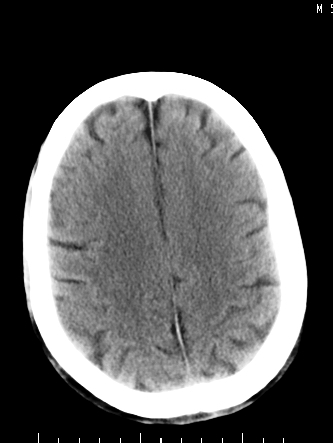

m/50,头昏头痛1月,近3天感觉左半肢体活动不利,自述半年前呈患肺tb,腰穿脑脊液未见特殊改变。现做头颅ct请大家会诊。

考虑颅内感染性病变:结核可能性大。

结核性脑膜炎,结核瘤,梗塞灶三症并存,提示颅内结核感染可能性大。

右侧基底节区缺血性脑梗塞.脑干区考虑结核.

可考虑结核,患者水肿范围大,囊性病灶边缘密度较高,不考虑胶质母细胞瘤